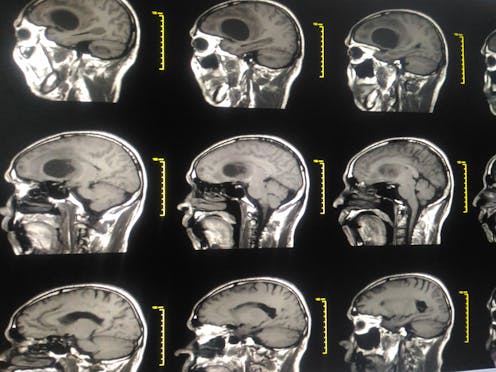

Brain cancers are fortunately rare tumours in adults. Nevertheless, the most common type of brain cancer, glioblastoma, is incurable and almost always lethal. Because of the lack of effective therapies, the average survival with glioblastoma is only 15 months. US senator, John McCain suffered from this form of tumour, as did former British MP Tessa Jowell, who was outspoken about the need for more experimental treatments.

Finding new and more effective therapies for glioblastoma is very difficult for many reasons. Glioblastoma cells can move far away from the main tumour into the healthy brain, which makes complete surgical removal of the cancer impossible. These cancers are typically also very resistant to current drugs and radiation therapy. As a result, glioblastomas usually regrow after treatment, and these “recurrent” tumours tend to resist all efforts to treat them and ultimately cause the patient’s demise.